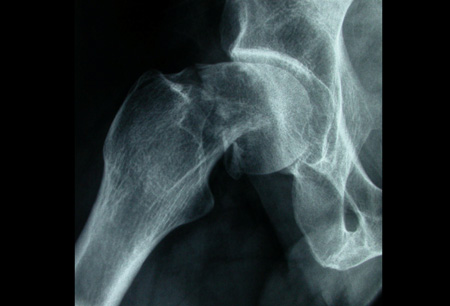

- Radiografías simples